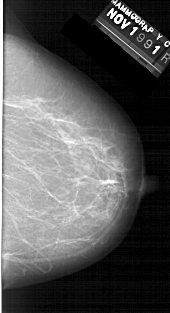

A_1324_1.LEFT_CC

LEFT_CC LINES 6511 PIXELS_PER_LINE 3586 BITS_PER_PIXEL 12 RESOLUTION 43.5 OVERLAY